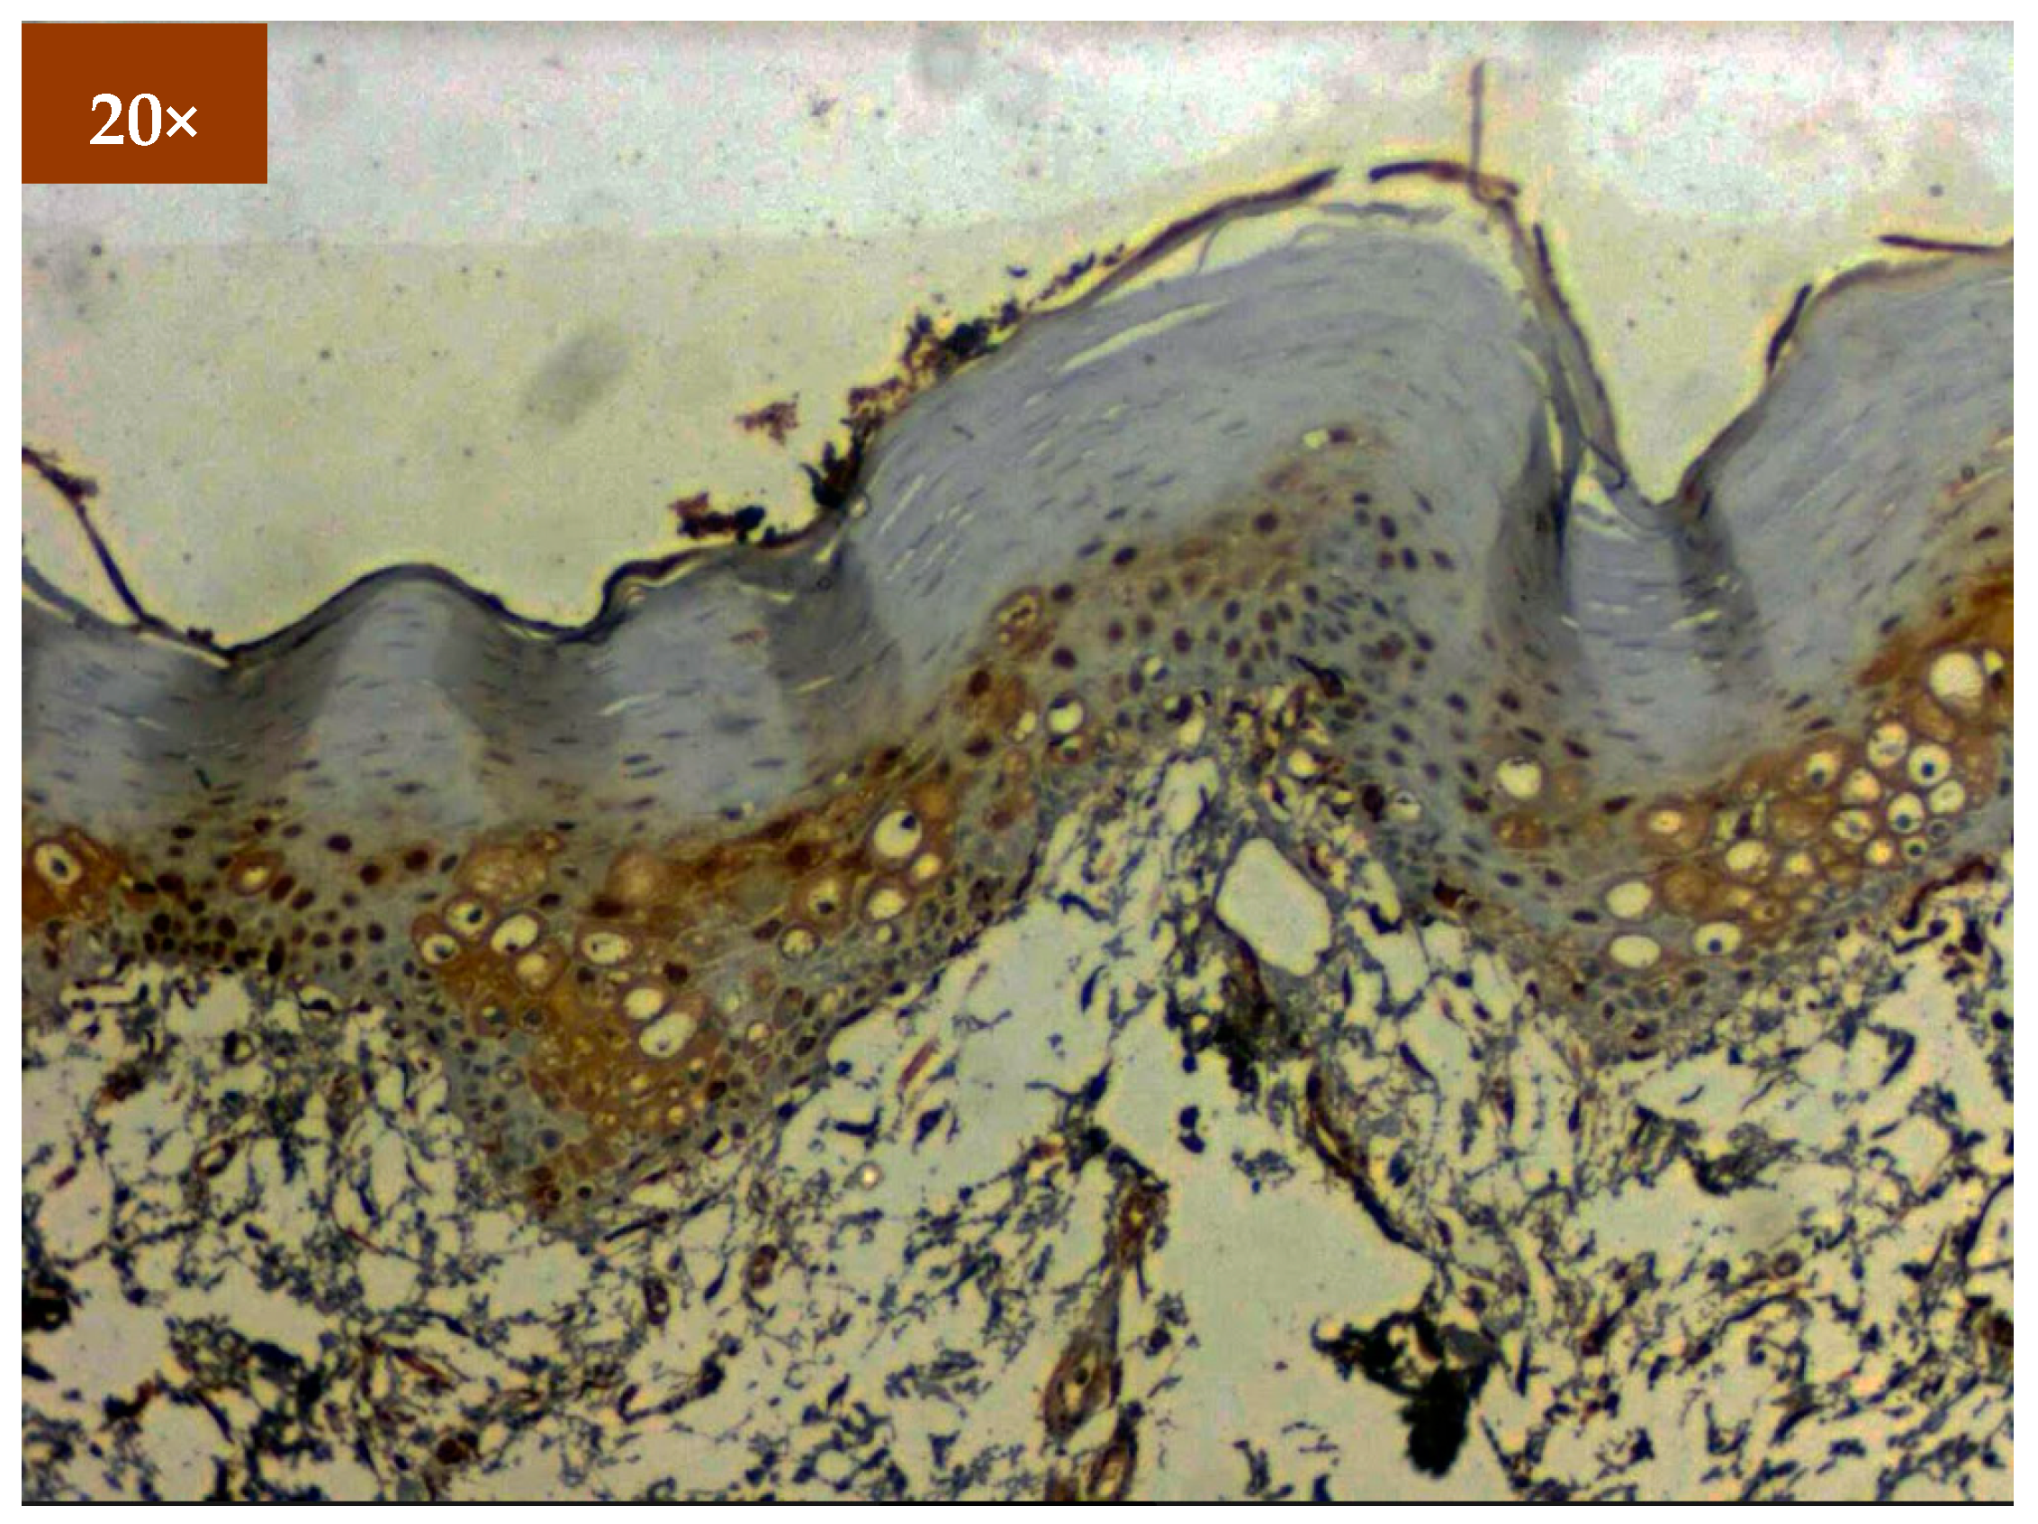

3.2. Immunohistochemistry

Expression of EGFR was studied in 173 patients in different age groups, in which mild positive immunoexpression was found in 23 patients (13.3%), intermediate positive immunoexpression was found in 51 patients (29.5%), strong positive immunoexpression was found in 87 patients (50.3%), and 12 patients (6.9%) tested negative (Table 2). EGFR overexpression was increased in oral cancer and OSMF compared to healthy controls (p = 0.000; χ2 = 68.620). EGFR overexpression was significantly correlated (p = 0.000; χ2 = 85.409) with various grades of dysplasia, and well-differentiated (WDSCC) and moderately differentiated squamous cell carcinoma (MDSCC) (Table 3). Figure 3 shows the expression of EGFR in healthy controls showing negative expression. Figure 4 shows the expression of EGFR in OSMF, showing intense cytoplasmic and nuclear positivity. Figure 5 and Figure 6 show the expression of EGFR in dysplasia and OSCC samples, respectively, showing intense cytoplasmic and nuclear positivity.

Figure 4.

IHC of EGFR in OSMF samples (under 20× magnification).

Figure 5.

IHC for EGFR in dysplasia (under 20× magnification).